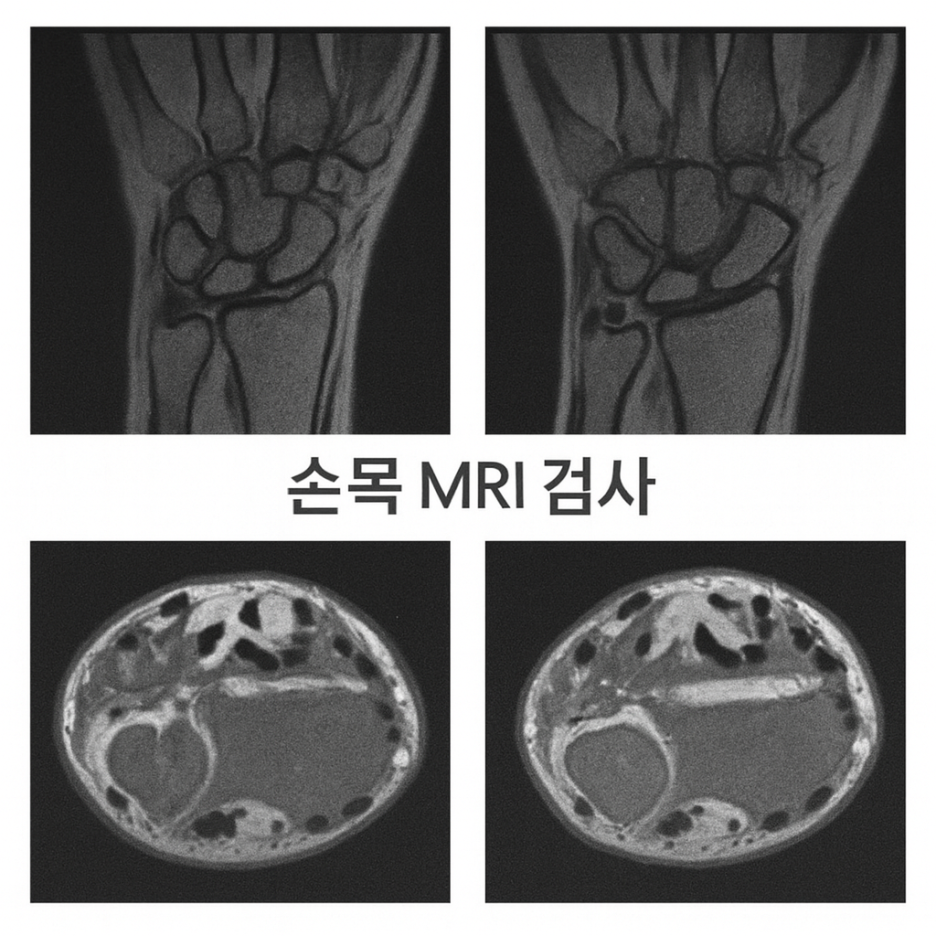

삼각섬유연골파열은 어떻게 진단하나요?

- 전문의 진찰을 통한 손목 움직임 및 통증 부위 확인

- MRI 촬영으로 TFCC(삼각섬유연골 복합체) 손상 여부를 확인

- 관절내시경을 통한 직접 관찰이 가장 확실한 진단 방법으로 알려져 있습니다.

Q. 손목 통증이 있는데 꼭 MRI까지 찍어야 하나요?

A. 단순 염좌와 감별이 어렵기 때문에 정확한 진단을 위해 MRI 검사가 도움이 됩니다.